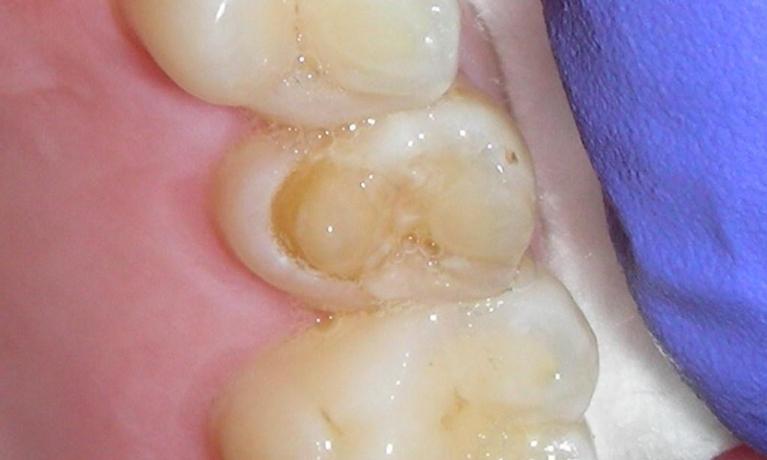

Diagnosis with theLED Transilluminator

The LED Transilluminator is an exciting new instrument that can let us “see into the inside of a tooth by lighting it up like a light bulb.

While in no way does it eliminate the need for dental X-rays, it provides another tool to diagnose decay, cracks and other conditions that might be missed by other methods.